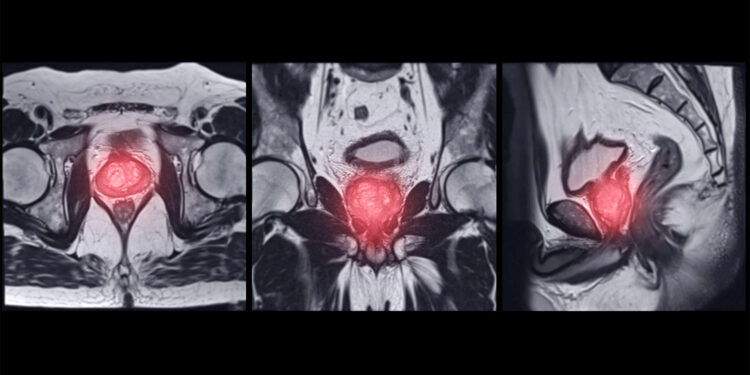

(MedPage Today) — Despite technologic advances and guideline recommendations, prostate MRI still lacks the accuracy to replace biopsies in active surveillance, data on almost 2,000 patients suggested.

MRI had a 75% negative predictive value …